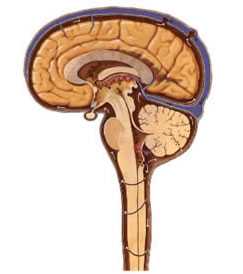

В норме ликвор (цереброспинальная жидкость) вырабатывается сосудистыми сплетениями сообщающихся между собой желудочков головного мозга. Наибольшее его количество образуется в боковых желудочках, откуда ликвор поступает в III желудочек, а из него по сильвиевому водопроводу в IV желудочек. Затем ликвор попадает в субарахноидальное (подпаутинное) пространство, которое простирается над всей поверхностью головного мозга, а в каудальном направлении проходит область краниовертебрального перехода и дальше окружает спинной мозг на всем его протяжении. Находящаяся в субарахноидальном пространстве цереброспинальная жидкость постоянно всасывается арахноидальной (паутинной) оболочкой спинного и головного мозга и попадает в кровь. Указанные выше этиологические факторы, нарушающие выработку, движение и всасывание ликвора, приводят к ее избыточному накоплению и возникновению гидроцефалии.

Выработка спинномозговой жидкости (ликвора) осуществляется грануляциями в желудочках головного мозга.